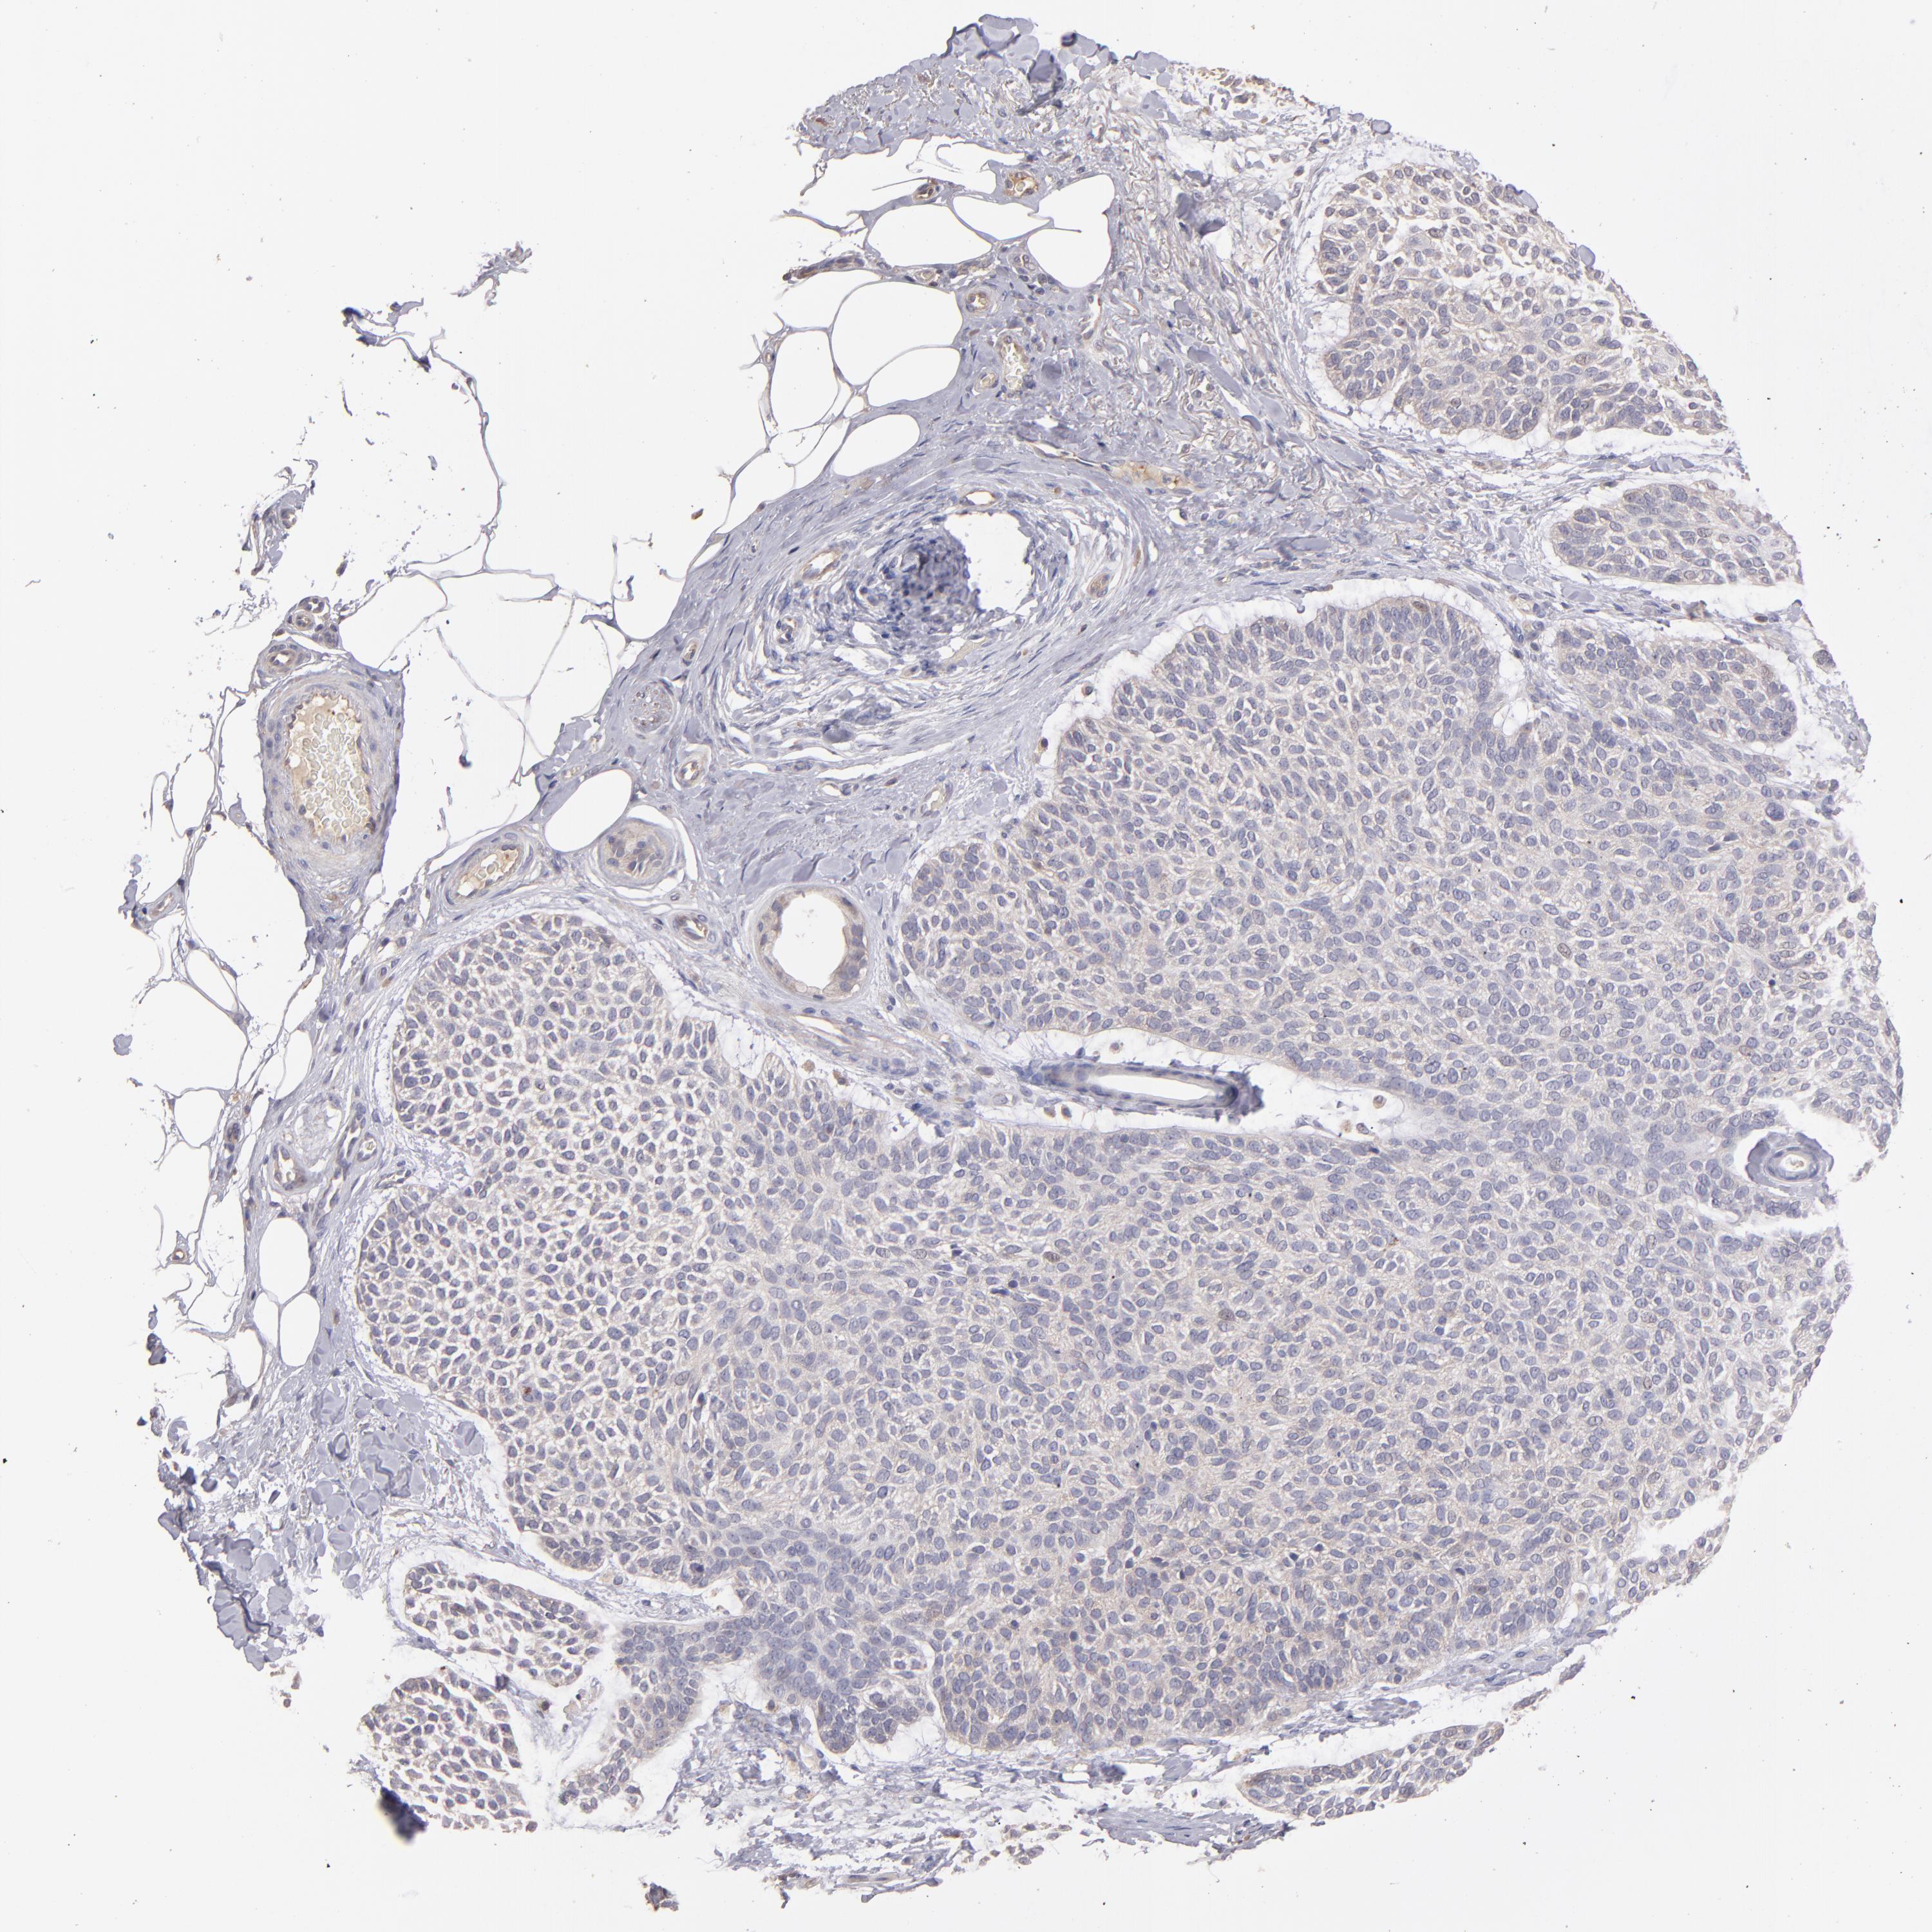

SKIN CANCER - Protein expressioni

A mouse-over function shows sample information and annotation data. Click on an image to view it in a full screen mode. Samples can be filtered based on level of antibody staining by selecting one or several of the following categories: high, medium, low and not detected. The assay and annotation is described here.

Antibody staining in the annotated cell types in the current human tissue is reported as not detected, low, medium, or high, based on conventional immunohistochemistry profiling in selected tissues. This score is based on the combination of the staining intensity and fraction of stained cells.

Each image is clickable and will lead to virtual microscopy that enables deeper exploration of all samples and also displays staining intensity scores, fraction scores and subcellular localization as well as patient and tissue information for each sample.

Antibody HPA003011

Squamous cell carcinoma, NOS